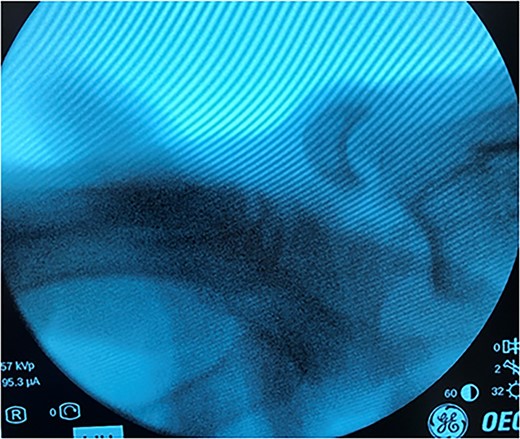

After medical optimization, the patient underwent PRC, open reduction internal fixation (ORIF) of the right distal radius fracture, and carpal tunnel release. A dorsal approach was used, with the third and fourth extensor compartments being released. At this point, extensive disruption of the dorsal wrist capsule and proximal carpal row was observed. The lunate was identified, noted to be devoid of soft tissue attachments, and was able to be excised. Completion of the PRC was achieved by excising the scaphoid and triquetrum from their minimal remaining soft tissue attachments entirely through the dorsal approach (Fig. 3). The lunate fossa of the radius, proximal capitate, and radioscaphocapitate ligament (prerequisite for successful acute PRC) was noted to be intact [2].

AP and lateral views immediately postop demonstrating right distal radius fixation and PRC.